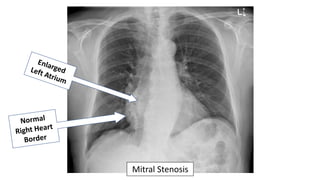

Valvular Heart Disease

Which cardiac chamber is enlarged in patients with significant chronic

mitral stenosis?

• Right atrium

• Right ventricle

• Left atrium

• Left ventricle

Mitral Stenosis

• Left atrial enlargement from mitral stenosis